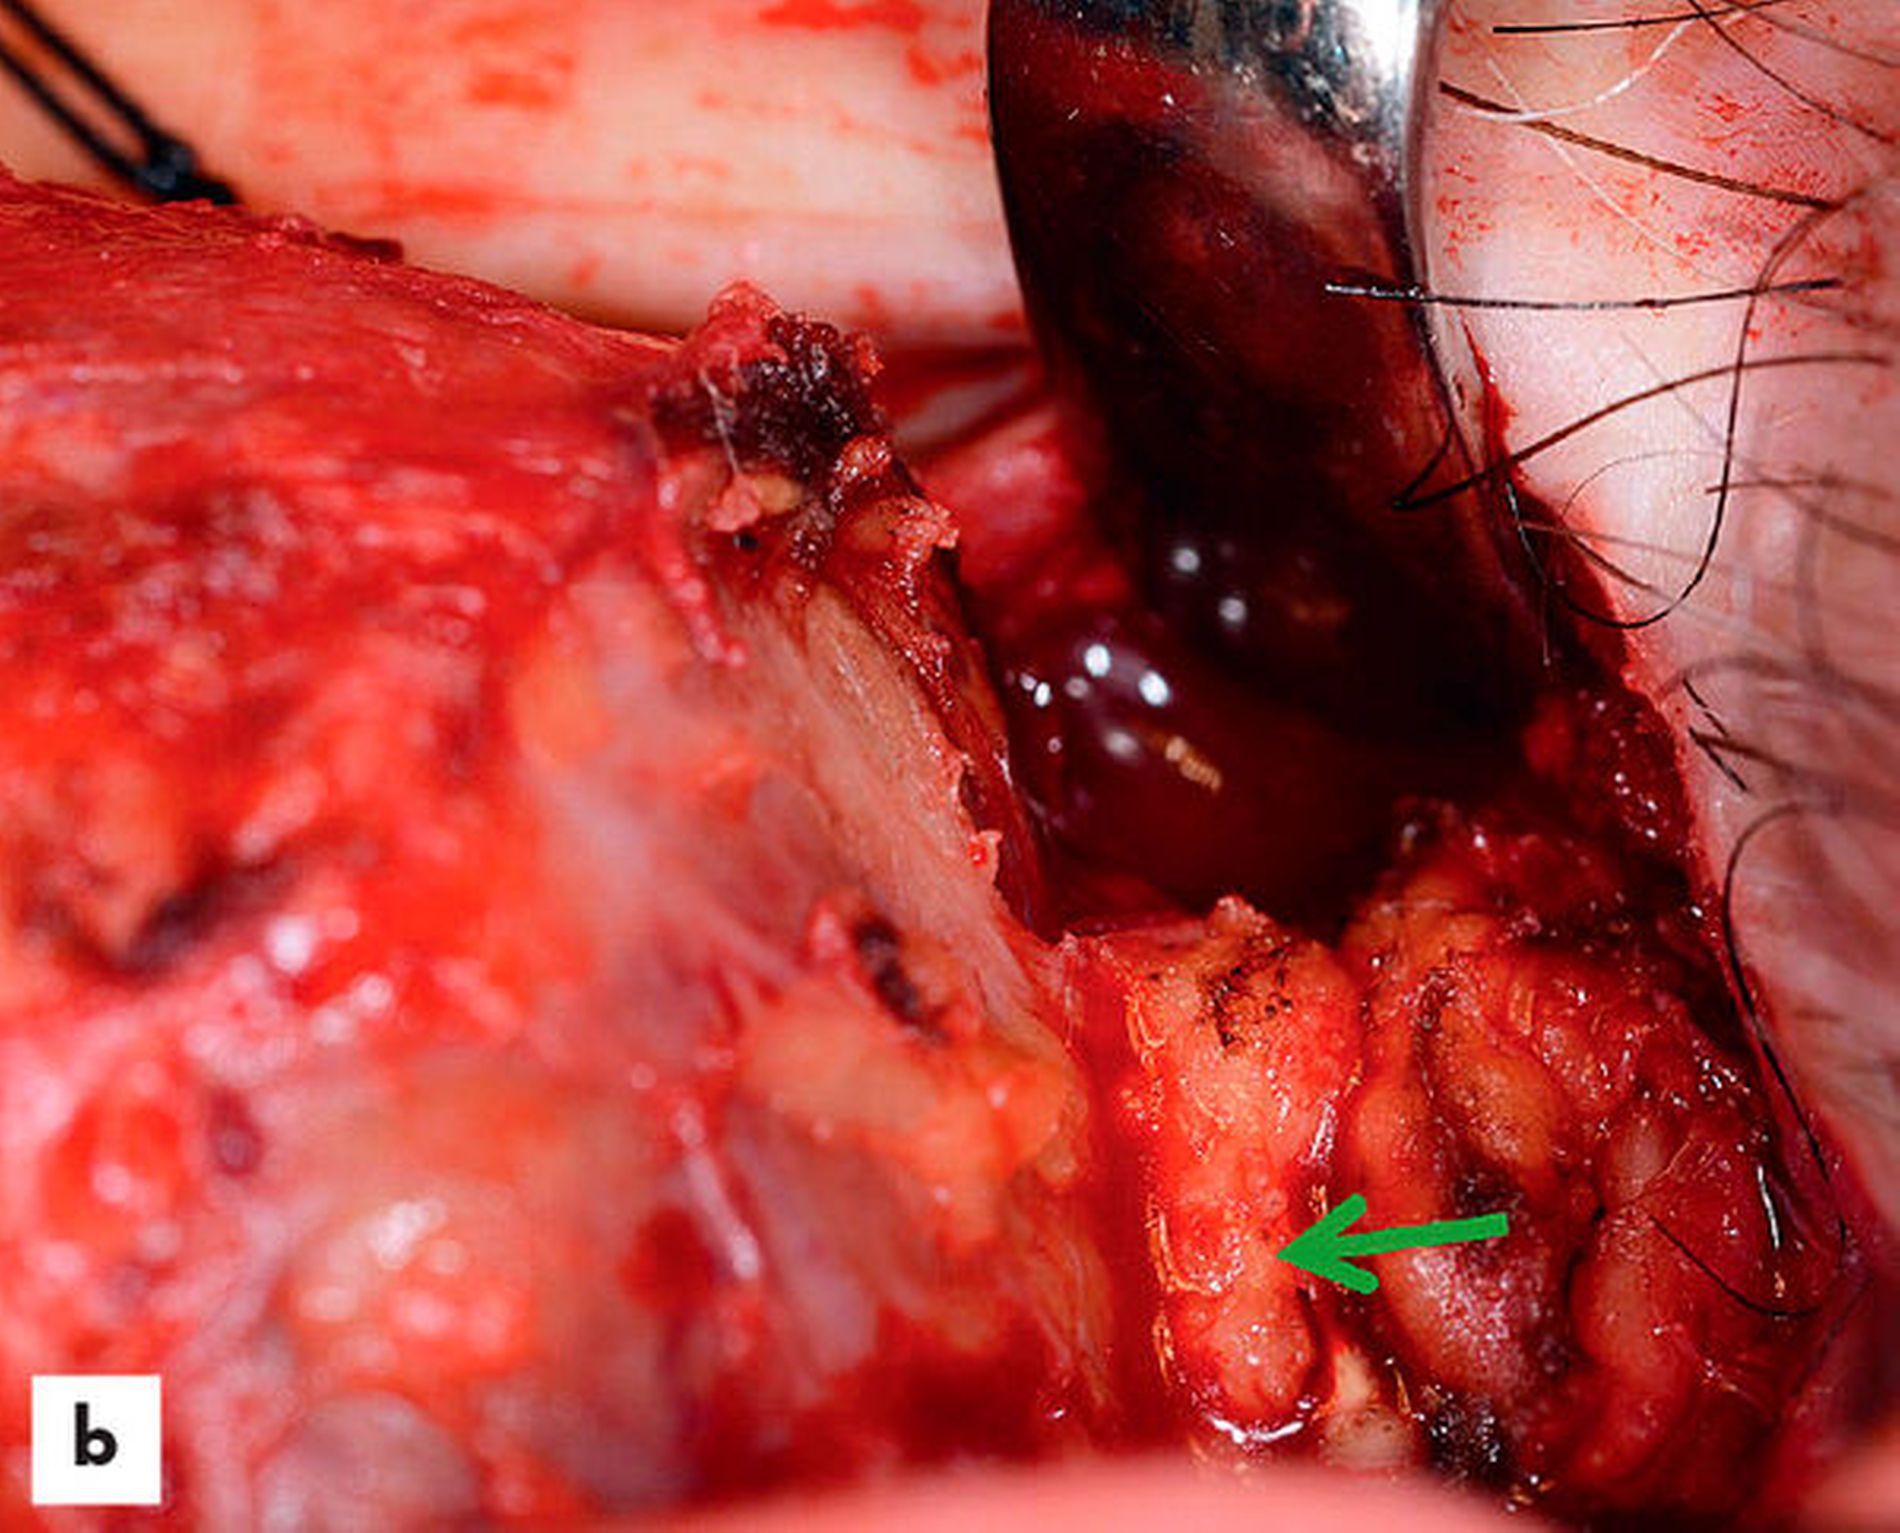

Der Tumor wurde in Vollnarkose unter Monitoring der Fazialisfunktion reseziert (Abbildung 3a).

Hierbei wurde über den alten Zugang die bindegewebig umschiedene, gut abgrenzbare Läsion entfernt. Der Nervus facialis war dem Tumor narbig am Oberpol angehaftet und wurde vom Tumor abpräpariert (Abbildung 3b).

Der Tumor konnte so vollständig entfernt werden (Abbildung 3c). Die histopathologische Beurteilung zeigte monomorphe, basaloid gepackte Zellen mit umgebender Kapsel. Dies entsprach dem Befund eines Basalzelladenoms der Speicheldrüse.